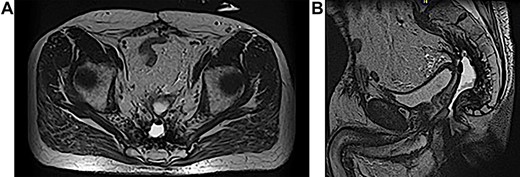

A 63-year-old male presented to the Colorectal Surgery Clinic complaining of constant sanguineous, mucous drainage from a chronic perineal sinus tract. He has a history of T2N1 rectal cancer status post neoadjuvant chemoradiation followed by low anterior resection 17 years prior to presentation complicated by a chronic anastomotic leak. Management of the anastomotic leak required a transverse loop colostomy with subsequent takedown and creation of a diverting loop ileostomy. One year prior to presentation, he underwent exploratory laparotomy with total proctocolectomy and abdominoperineal resection for simultaneous distal loop ileostomy stricture and a stricture at the low anterior resection anastomosis with chronic anastomotic leak, rectal bleeding and mucus drainage. Biopsies were taken at that time given concern for pelvic recurrence which showed benign lymph nodes, fat necrosis and abscess. Since surgery, the patient reported bleeding from a perineal wound and constant passage of mucus. Magnetic resonance imaging (MRI) 1 month prior to clinic presentation showed a retained 2–3 cm sinus cavity in the pelvis with a connecting tract to the perineum (Fig. 1A and B). Exam in clinic revealed a perineal wound with a sub-centimeter cutaneous opening and scant mucous drainage (Fig. 2). Given the MRI findings and significant lifestyle disturbances caused by the chronic drainage, he was scheduled for an exam under anesthesia with endoscopic cauterization of the sinus cavity lining in hopes of obliterating the cavity epithelium.

Physical exam in office showing perineal wound with sub-centimeter cutaneous opening.